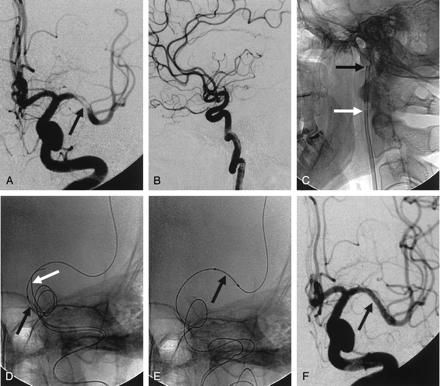

Double-wire technique.

A, Lateral left ICA angiogram shows >70% stenosis (arrow) of the supraclinoid portion.

B, Lateral magnified view shows that the balloon-mounted stent cannot cross the acute angle (arrow) of the cavernous ICA.

C, Navigation of the stent-delivery system into the target lesion (arrows) is successful.

D, Balloon-mounted coronary stent (arrows) is successfully deployed. No procedure-related complication occurred.

E and F, Anteroposterior (E) and lateral (F) left ICA arteriograms obtained immediately after stent placement show sufficient and smooth dilatation of the stenotic segment.